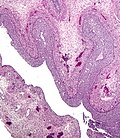

Microscopic

Features:[9]

- Collection of eosinophilic (i.e. pink) cuboidal cells; usually solid, may be cystic.

- Elliptical nucleus with single groove along major axis; "coffee bean" nucleus -- key feature.

Location:

- Usually in soft tissue of the uterine tube.